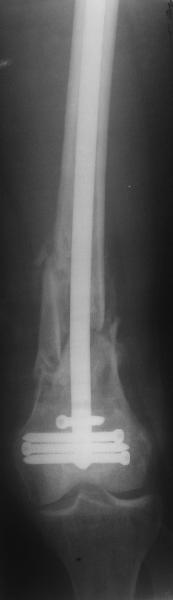

Антеградный остеосинтез при дистальных переломах бедра мы применяем давно, этот материал обобщен в канд. диссертации Александра Виноградского.

Предприятие ЦИТО выпускает доработанные нами гвозди, которые хорошо годятся для дистальных переломов, да и недороги. Можно вводть в дистальное овальное отверстие 3 винта, которые заклинивают друг друга.

Большеберцовые стержни отлично выполняют роль ретроградных бедренных. Конечно, которые не 9, а 12 мм в диаметре.

Примеры приложены.